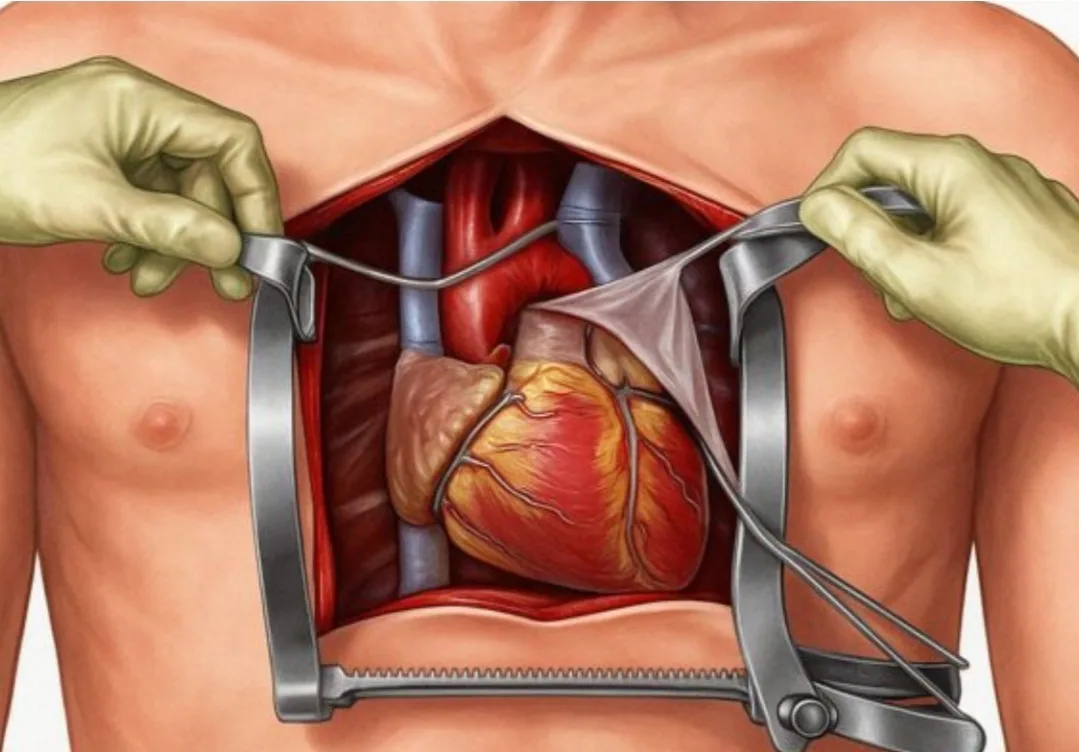

ويتيح هذا التطور الطبي للأطباء إمكانية استهداف مناطق الخلل بدقة عالية قبل إجراء التدخل الجراحي، ما يقلل من الحاجة إلى الاستكشاف داخل الجسم خلال العمليات، ويجعل الإجراءات أكثر أمانًا وأقل توغّلًا.

ويرى خبراء أن هذه التقنية قد تشكل نقلة نوعية في علاج أمراض القلب، خاصة في حالات اضطرابات النظم القلبي، إذ تمكّن من التخطيط المسبق للجراحة بشكل دقيق وشخصي لكل مريض على حدة.